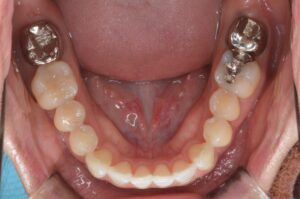

治療後

| 治療内容 | 上下の前歯のずれを主訴に矯正治療希望にて受診。インビザラインを用いて、矯正治療を行なった。途中1回の追加治療を行い、左上前歯部にジルコニアのブリッジを装着し保定に移行。 |